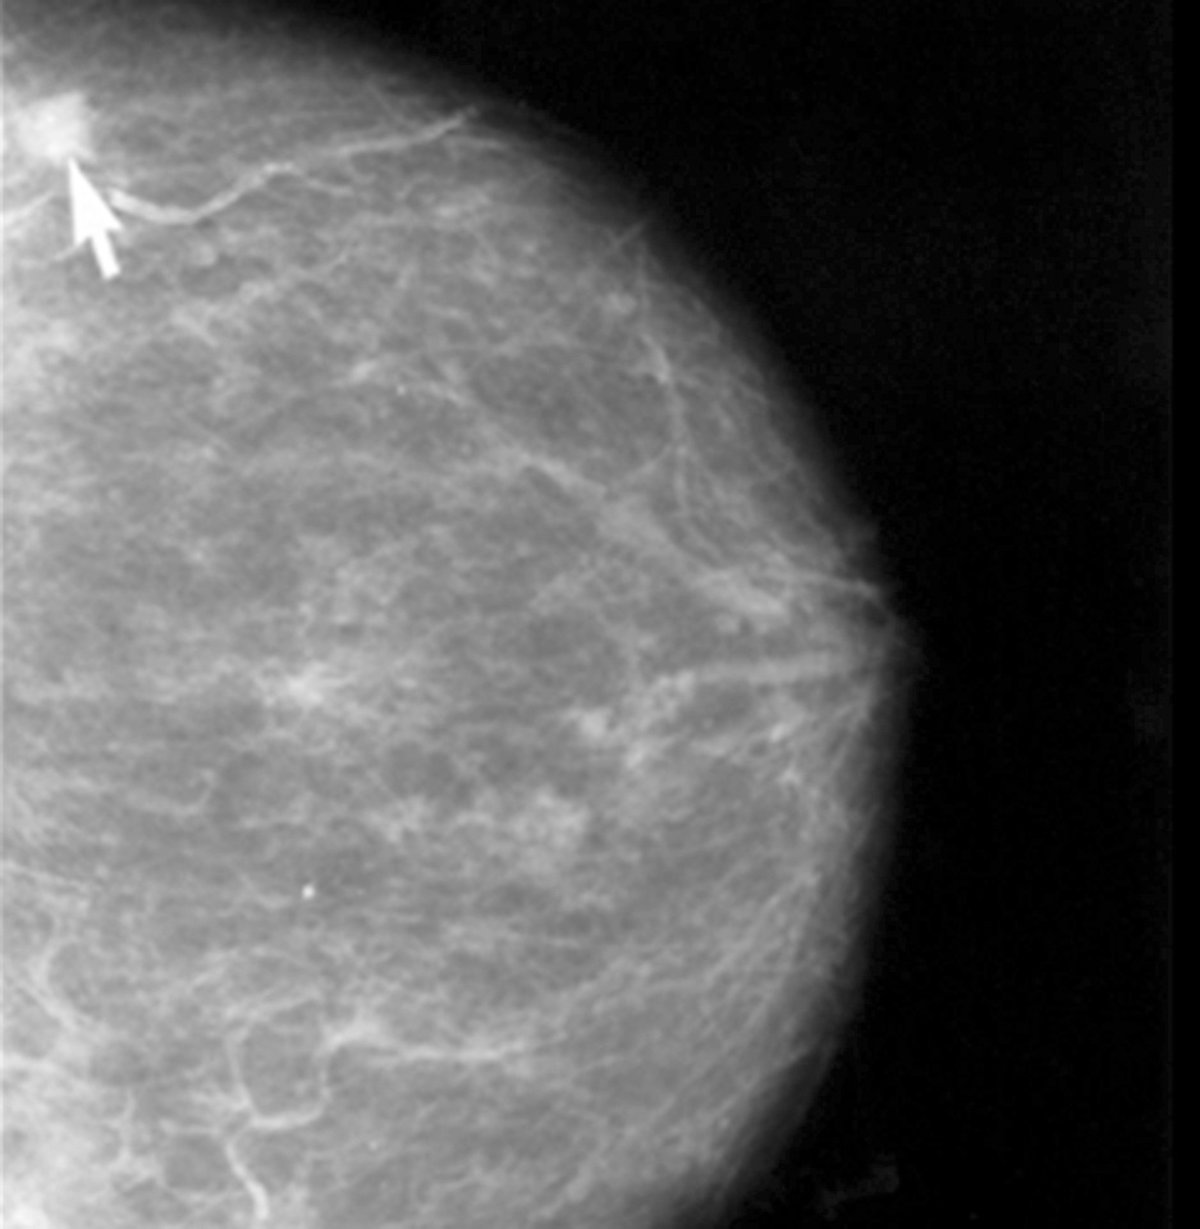

Diseñan nanodispositivos de liberación controlada de fármacos contra el cáncer de mama

Investigadores de la Universitat Politècnica de València, el Instituto de Investigaciones Biomédicas 'Alberto Sols' (CSIC-UAM), la Universitat de València y el CIBER de Bioingeniería, Biomateriales y Nanomedicina (CIBER-BBN) han desarrollado, a escala de laboratorio, nuevos nanodispositivos que permiten la liberación controlada de fármacos --en concreto, doxorrubicina--- para terapias contra el cáncer de mama.